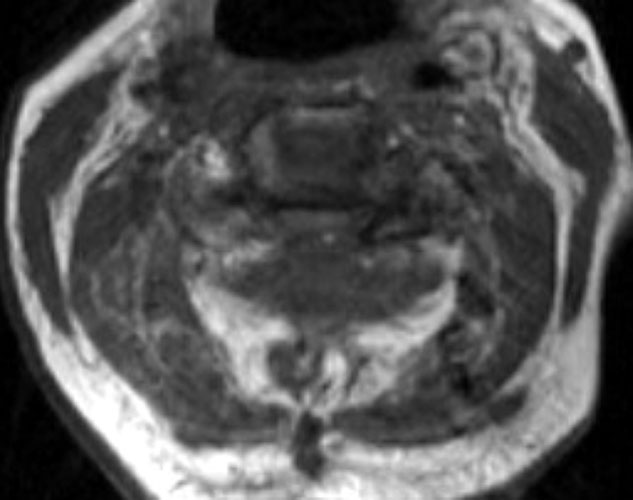

A B C

Non-enhanced sagittal T1 (A), sagittal T2 (B) and axial T1 images demonstrate a large fluid collection, predominantly low signal on T1, bright on T2 with a few areas of T1 hyperintesity mixed within. These constellation of findings are consistent with a post-operative epidural hematoma with blood products of various ages. There is severe severe spinal canal stenosis at C3-4, and very severe spinal canal stenosis at C4-5 and C5-6. The cord is markedly flattened in the anterior-posterior dimension, to approximately 2-3 mm secondary to mass effect from this fluid collection. There is abnormal T2 weighted hyperintensity within the substance of the cord at the C5-6 and C6-7 levels, consistent with some edema.